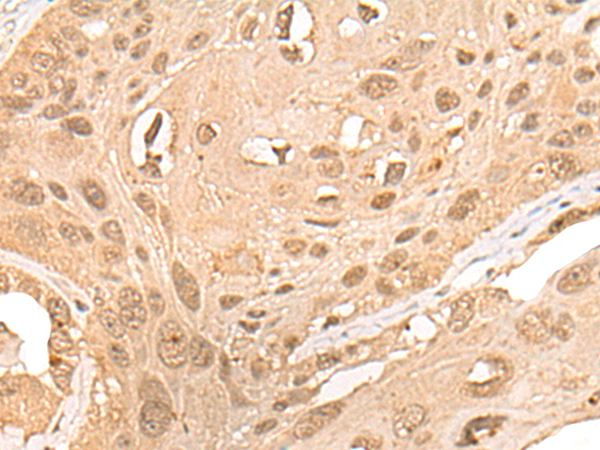

The image is immunohistochemistry of paraffin-embedded Human esophagus cancer tissue using 46981(CPNE7 Antibody) at dilution 1/20. (Original magnification: ?00)